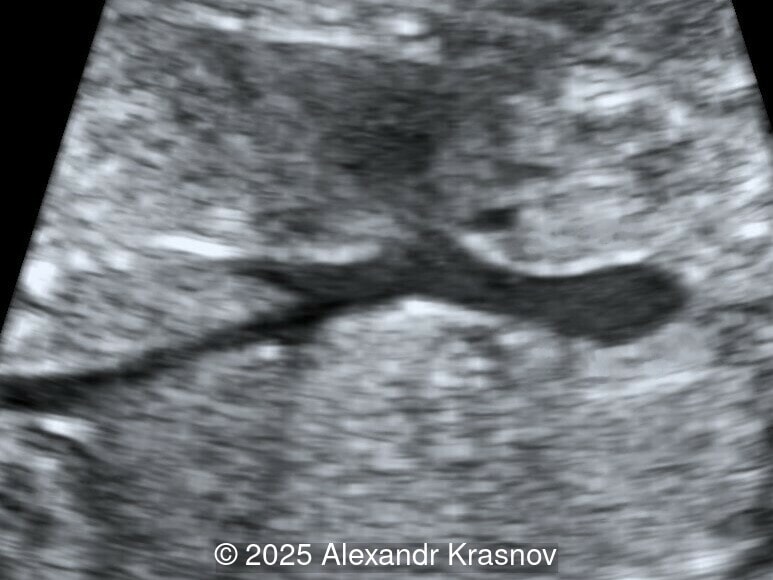

Image 3

Our ultrasound showed biometry data corresponding to 21 weeks of gestation. During echocardiography, an abnormal drainage of the pulmonary veins was detected in which the pulmonary veins drain into a venous collector linked to the superior vena cava. The four-chamber view and the three-vessel view were altered and raised suspicion of a pathology. The grayscale and color Doppler images of the four-chamber view indicate a smooth posterior wall of the left atrium, increased distance between the left atrium and the descending aorta and the absence of pulmonary veins entering the left atrium (Image 1, 2; Video 1, 2). In the three-vessel view, the diameter of the superior vena cava appears larger than that of the aorta (Image 3, Video 3). In the images of the venae cava, a significant difference is seen between the diameters of the inferior and superior vena cava with significant enlargement of the superior vena cava (Image 4, Video 4). Additionally, there is a pulmonary venous confluent chamber (“twig sign”) behind the left atrium (Image and Video 5). A vertical ascending vein connects the confluent chamber with the superior vena cava where it drains blood from the pulmonary veins (Images 6, 7; Video 6).